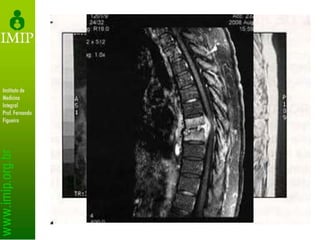

Exames secundários

• RNM

– Determina extensão da infecção

– Identifica tecidos acometidos

– Não identifica etiologia

• Não exclui biópsia

• RNM facilita a distinção entre tuberculose

e tumor

– Presença de abscesso e fragmentos ósseos